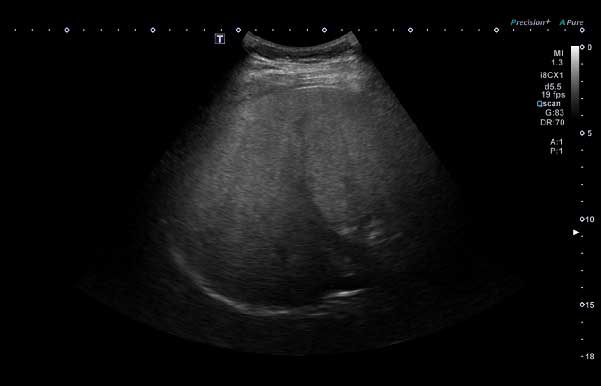

소아 지방간이 의심되면 혈액 검사와 문진, 신체 진찰 후 영상 검사를 시행한다. 가장 기본은 복부 초음파 검사로, 이를 통해 간에 지방이 얼마나 축적돼 있는지 확인할 수 있다. 경우에 따라 간 섬유화(딱딱한 흉터 조직)정도를 평가하는 탄성 초음파나 MRI(자기공명영상) 검사를 추가하기도 한다. 간 조직 검사는 제한적인 경우에만 시행된다.